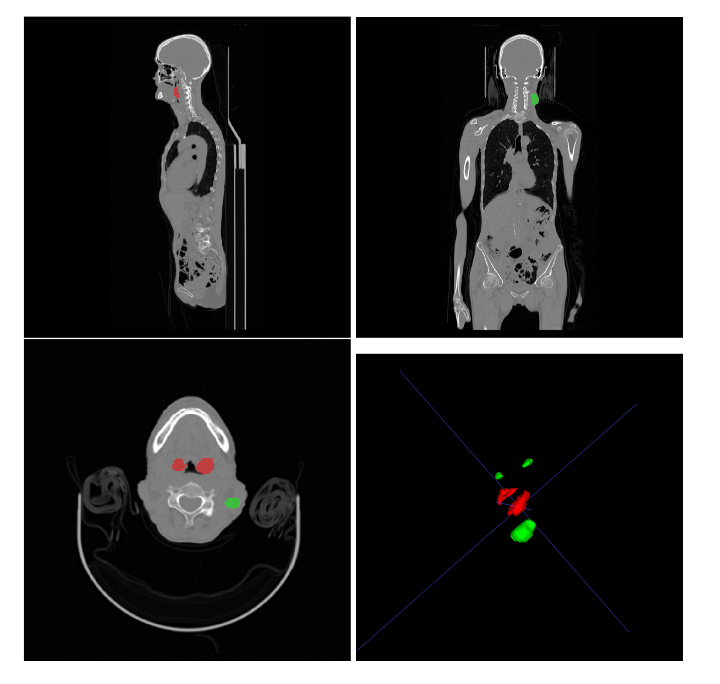

Research Highlights

• Researchers from NVIDIA won 1st place on the HECKTOR22 challenge leaderboard- a platform for researchers to compare their solutions to segmentation of tumors and lymph nodes from 3D CT and PET images. They re-sampled all images to a common resolution, cropped  around head and neck region, and trained SegResNet semantic segmentation network from MONAI. They used 5-fold cross validation to select best model checkpoints.  An ensemble of 15 models from three runs made up the final submission.

Image of 1st place solution